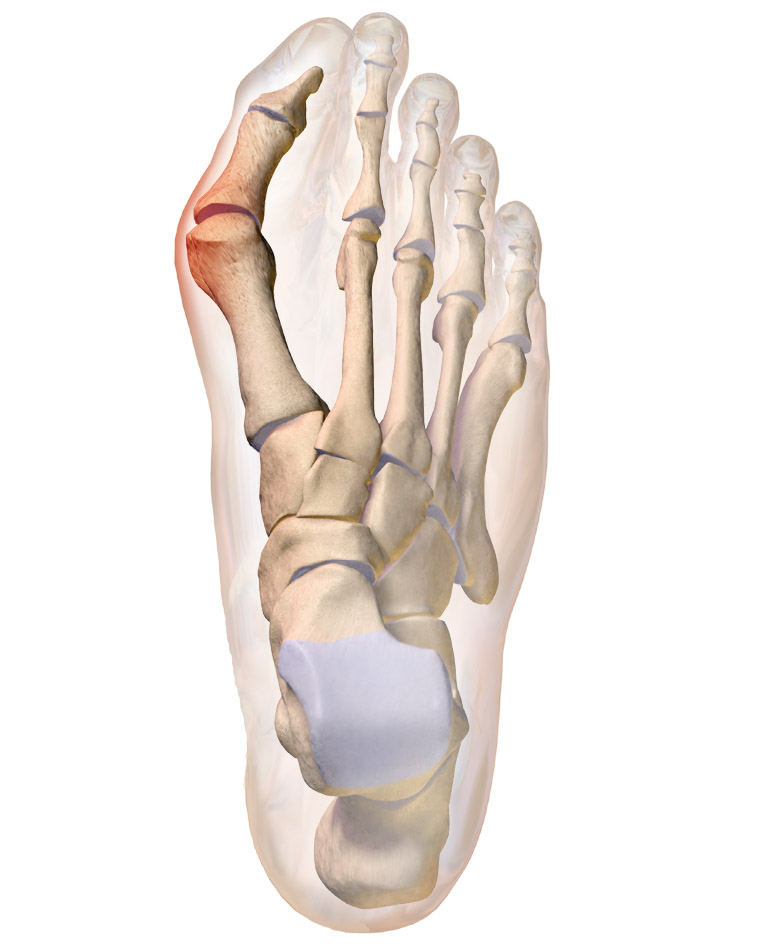

외반모지는 정확한 원인이 밝혀지지 않았지만, 내적 요인과 외적 요인이 복합적으로 작용하여 발생하는 것으로 알려져 있다.[3][8] 발등 안쪽의 첫 번째 중족골이 안쪽으로 휘고 엄지발가락이 바깥쪽으로 꺾이면서 엄지발가락 뿌리 관절(제1MTP 관절)이 튀어나오는 것이 주된 증상이다.

발등 안쪽에 있는 첫 번째 중족골이 안쪽으로 휘고 엄지발가락이 바깥쪽으로 꺾이면 엄지발가락 뿌리 관절(제1MTP 관절)이 튀어나온다. 발에 맞지 않는 신발을 신으면 튀어나온 부분이 신발에 쓸려 통증이 생긴다. 여성에게서 많이 나타나며(90%), 특히 하이힐처럼 굽이 높고 앞이 좁은 신발을 장시간 신는 경우에 발생하기 쉽다고 알려져 있다.[20] 폭이 너무 넓은 신발을 신으면 발이 앞으로 미끄러져 발가락이 압박되어 발병하는 경우도 있다. 증상이 진행됨에 따라 보행이나 기립 시 통증을 느낄 수 있다. 외반모지가 되면 보행 시 엄지발가락에 제대로 하중을 가할 수 없어 두 번째나 세 번째 발가락 뿌리 부분의 발바닥에 하중이 집중되어 잘 낫지 않는 유통성 굳은살이 생기기도 한다. 어린이와 남성에게도 발생한다. 같은 요인에 의해 외반모지와 반대로 새끼발가락이 엄지발가락 방향으로 꺾이는 증상은 '''내반소지'''라고 불린다.